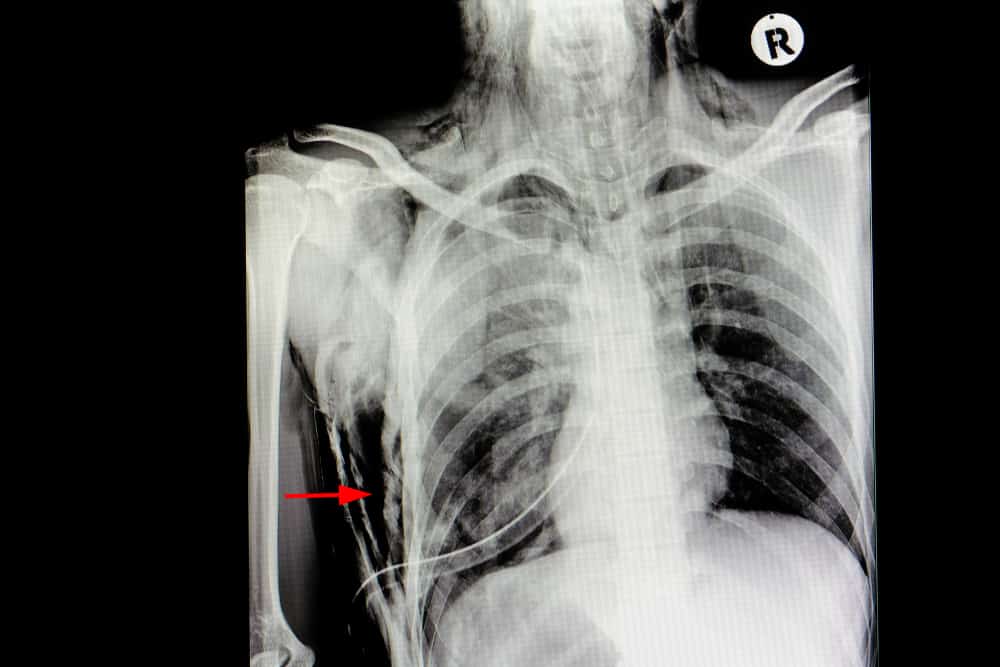

X-ray imaging and computed tomography (CT) scans are a few of the common tests that can help evaluate the prevalence of subcutaneous emphysema.

• Pneumothorax (a collapsed lung that may occur alongside a rib fracture)